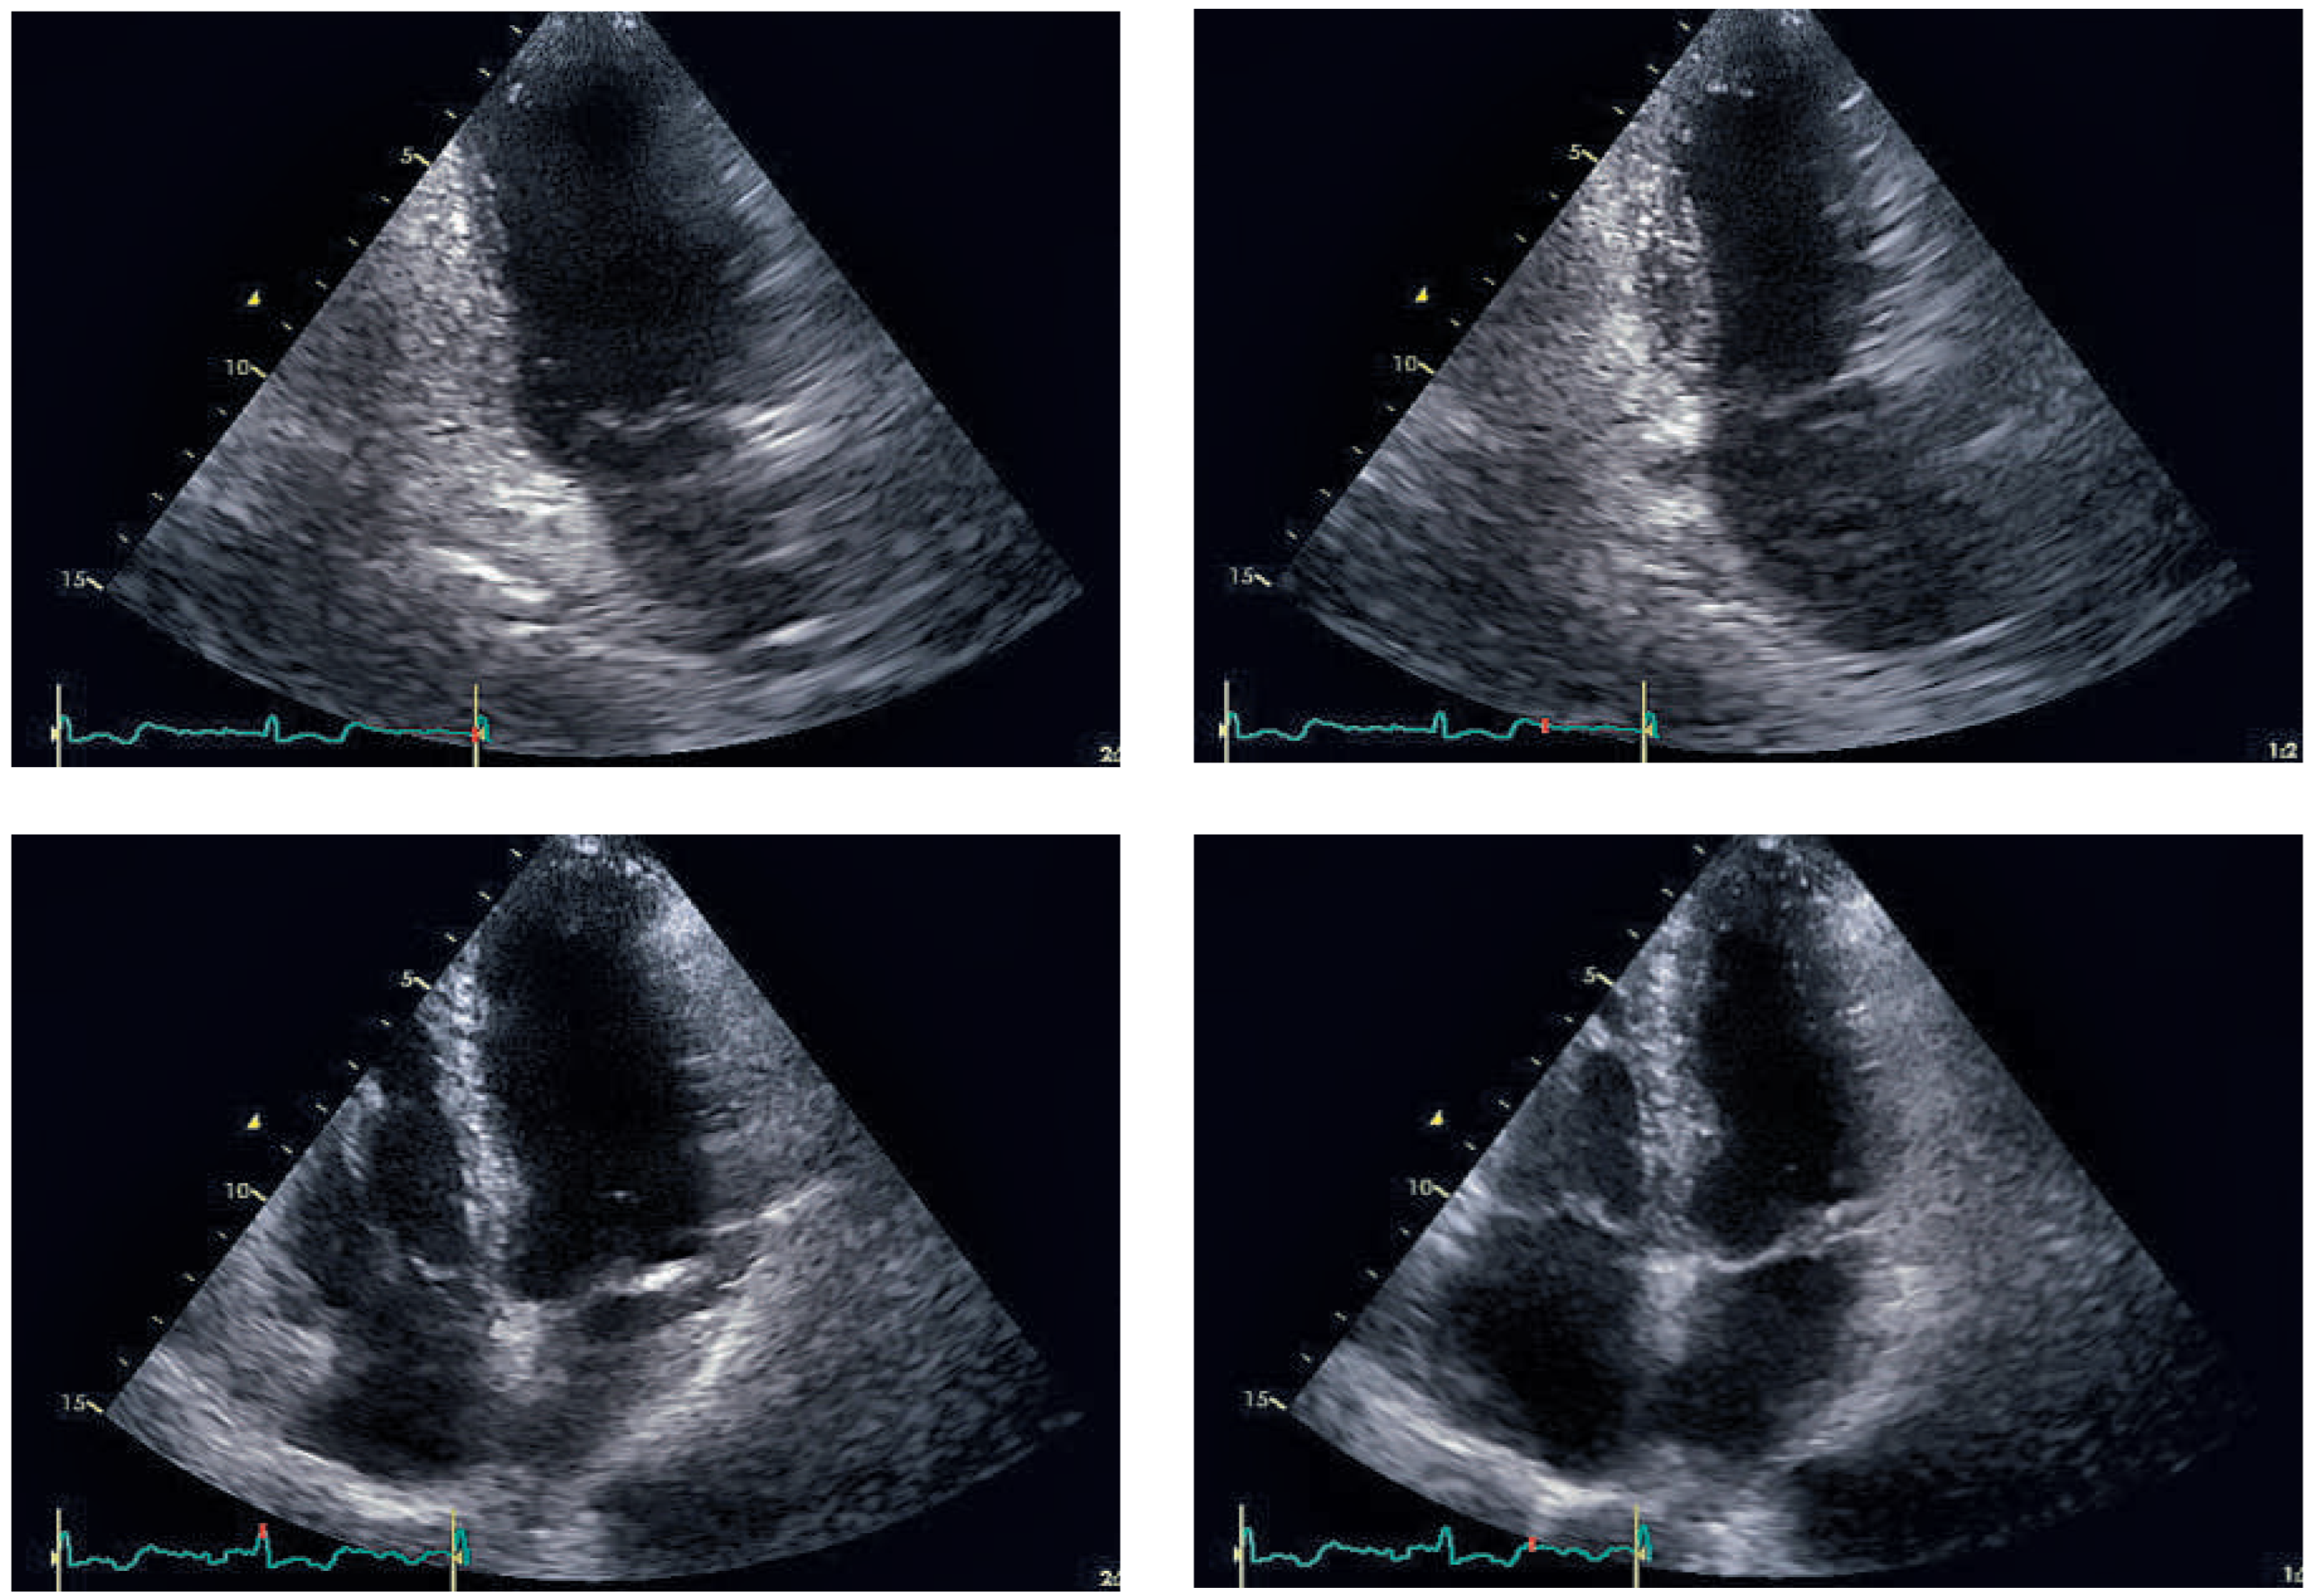

Figure 6. Echocardiographic follow-up after 4 weeks: End-diastolic (left side) and endsystolic (right side) frames of parasternal long axis (top row) and four-chamber view (bottom row). Left ventricular function recovered completely after 4 weeks.